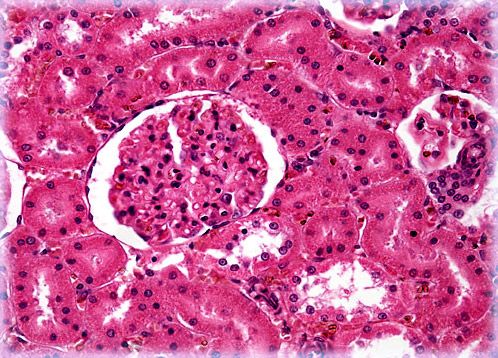

Mammalian Kidney

The kidney is an organ found in all vertebrates as well as some invertebrates. The primary functions of the paired bean-shaped structure include ridding the body of metabolic waste products and maintaining water balance and the proper chemical environment within the body.